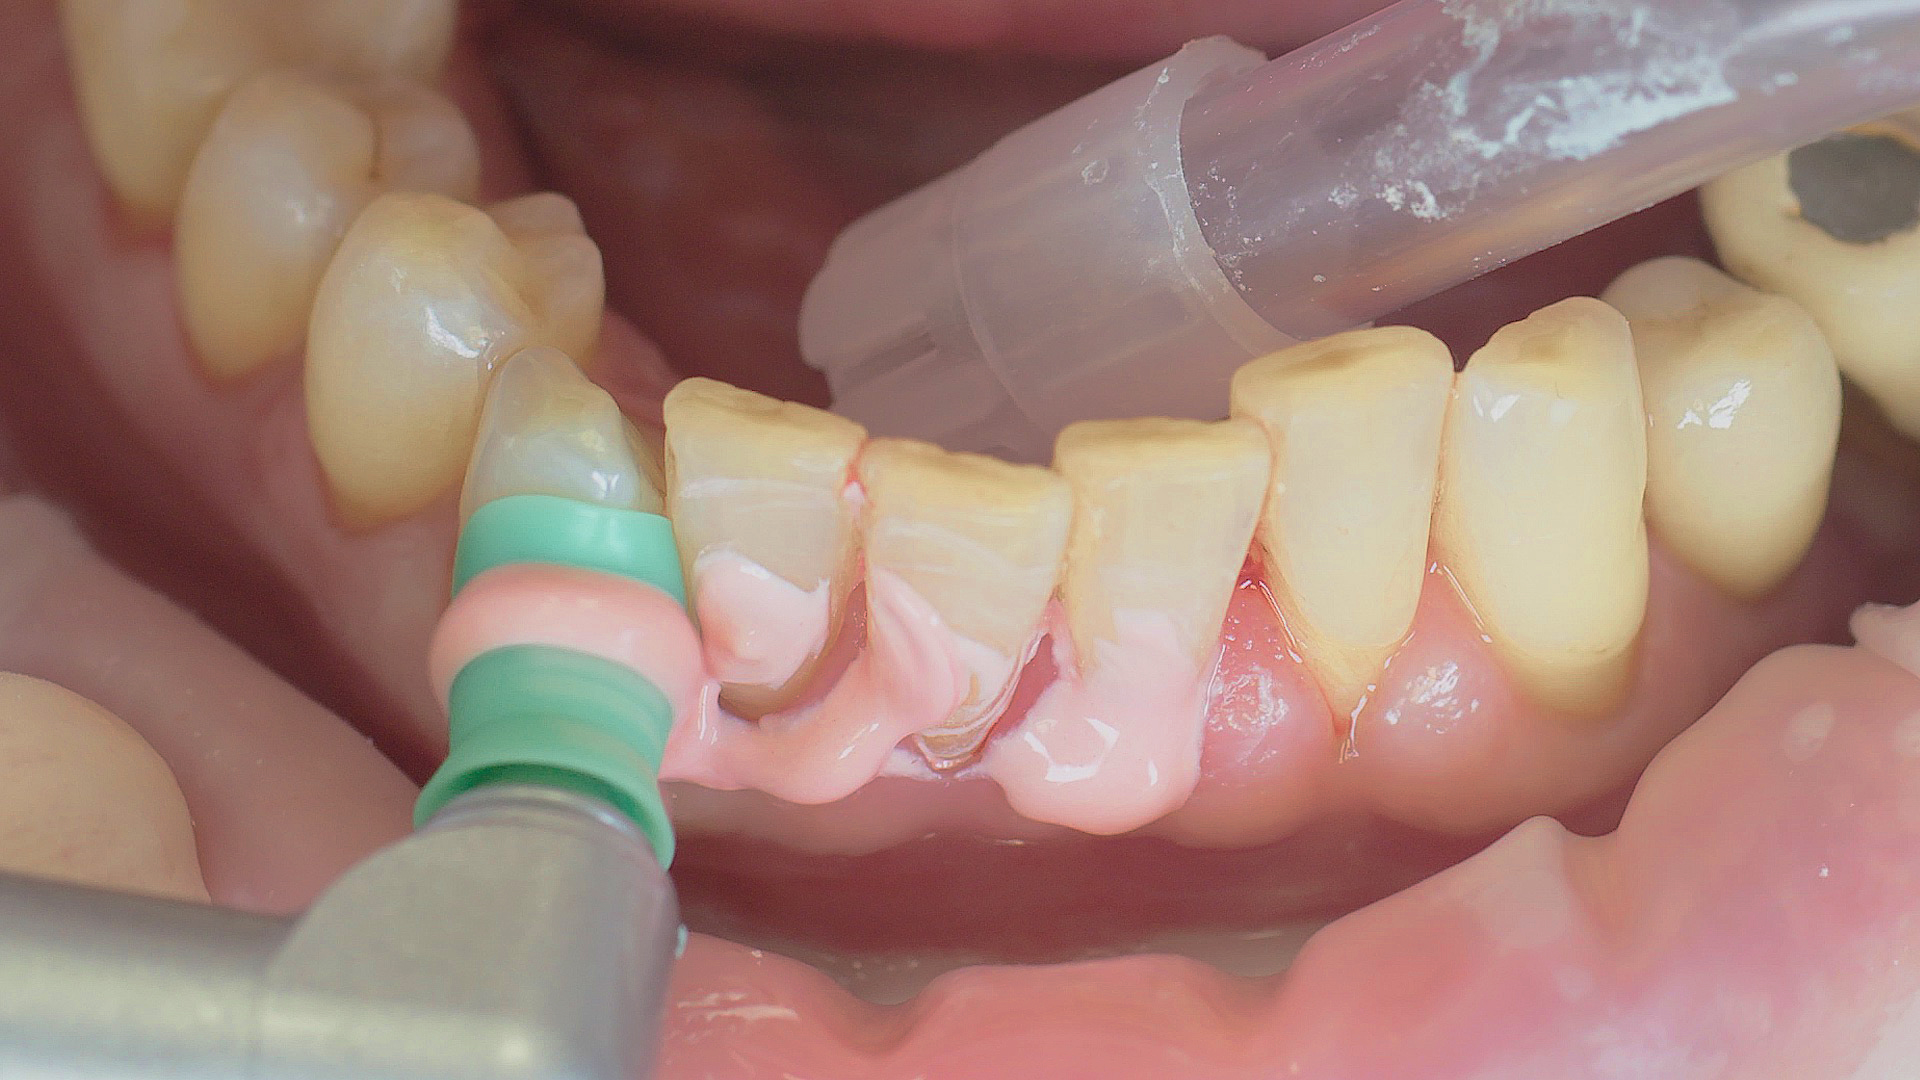

Every dental examination is based on a detailed medical history combined with targeted diagnostics con- taining as much detail as possible: The dentist records systemic risk factors such as diabetes or smoking and identifies any potential increased tendency to inflammation.[3] Hard and soft tissues are examined and periodontal pockets are probed in a screening test according to PSR (Periodontal Screening and Recording). In case of abnormal findings, the periodontal status is then re- corded and therapy is initiated where necessary. This treatment begins with professional biofilm management, by using, for example, rotary cups and polishing com pounds (Fig. 1), and comprehensive instructions in oral hygiene. Sonic or ultrasonic systems remain an effective alternative or supplement to manual instruments for sub- gingival debridement and biofilm management (presentation by Prof. Dr Ulrich Schlagenhauf; Fig. 2). Supplementary use of photodynamic therapy, air polishing or local and systemic antibiotics is not adequately documented (Prof. Dr Sema Hakki).[4] According to Dr Sergio Bizzarro, improved biomarker diagnostics may lead to an increase in customised patient therapy in the future.